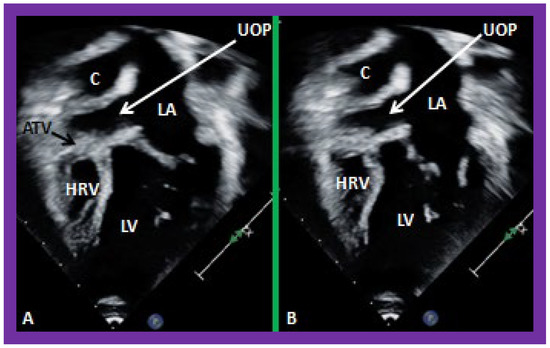

Post-Fontan echocardiographic anatomy is best displayed in apical four chamber views, as demonstrated in Figure 38, Figure 39 and Figure 40. The remnants of the RA and the LA are seen (Figure 38, Figure 39 and Figure 40). The remnants of atrial septum are not usually seen since the atrial septum is completely removed either during bidirectional Glenn or Fontan surgery. Unobstructed pathway allowing emptying of blood flow from the coronary sinus and thebesian veins is usually seen in an apical four chamber view (Figure 40).

Figure 40. Selected video frames from apical four-chamber views demonstrating unobstructed pathway (UOP) (long arrow) between the right and left (LA) atria; the mitral valve is closed in (A) while it is open in (B). ATV, atretic tricuspid valve; C, conduit; HRV, hypoplastic right ventricle; LV, left ventricle.

Applsci 11 09472 g040